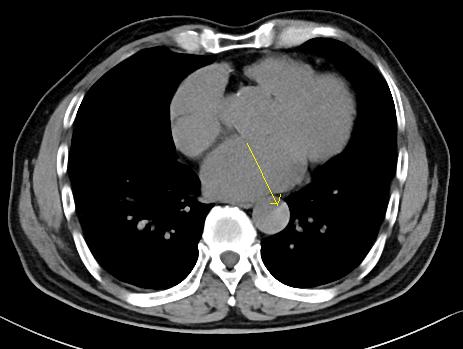

增强CT一看,吓到一大片!太惊悚了!

图6